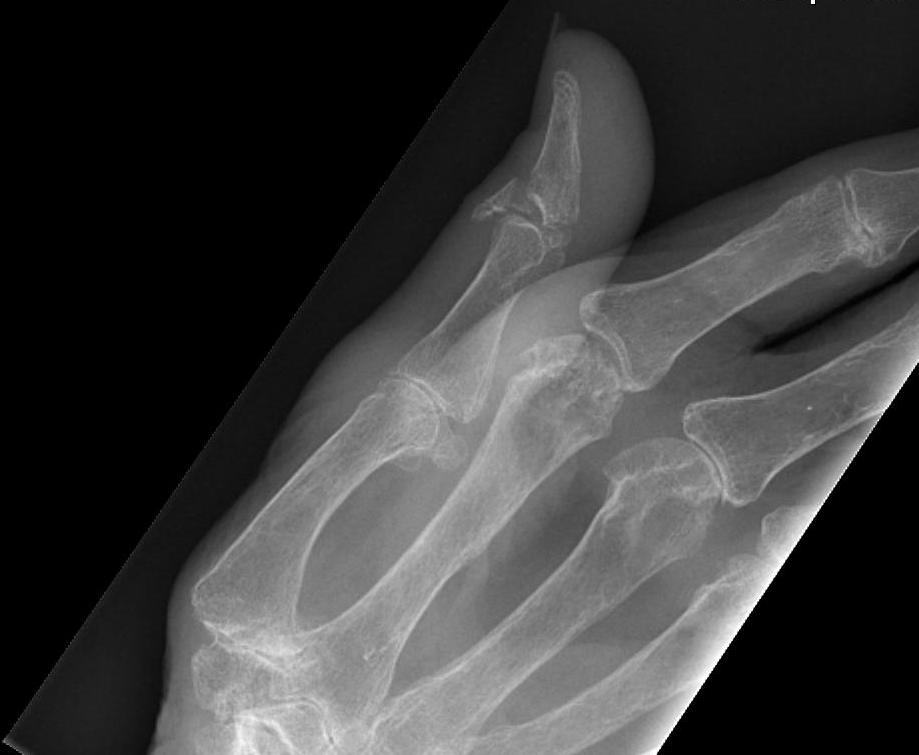

Type III - Swan Neck

- second most common

- primary deformity is OA and dorsal subluxation of CMC

- hyperextension MPJ / IPJ flex